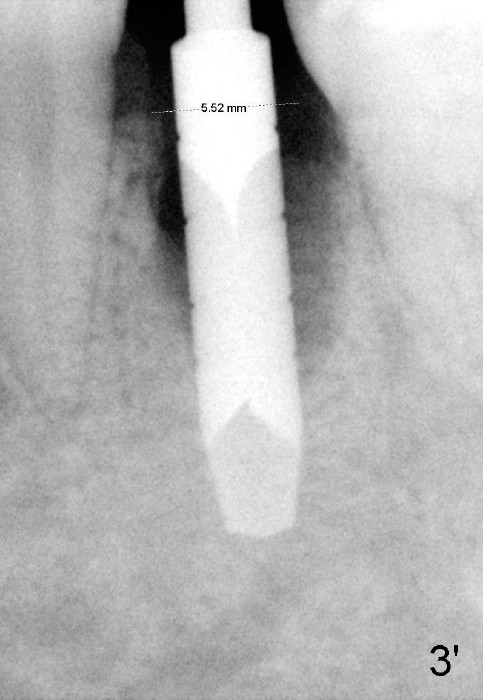

Fig.3: 3.5 mm reamer in place, 17 mm below the gingival margin. Dashed line: the mental loop.